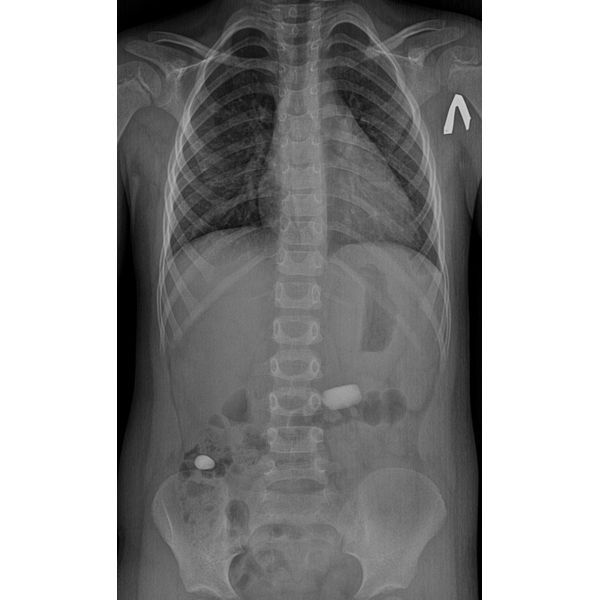

При внешнем осмотре патологические признаки не наблюдались, поэтому малыша направили на обзорную рентгенографию органов грудной клетки и брюшной полости.

Рентгенография показала:

- инородное тело овальной формы диаметром до 1,5 см, расположенное в правой части брюшной полости выше подвздошного гребня (верхнего края таза), но ниже печёночного угла;

- инородное тело неправильной прямоугольной формы с закруглёнными краями размером 1 × 1,5 см, которое находилось в верхнем левом квадранте живота (вблизи селезёнки, на уровне 4-го поясничного позвонка).